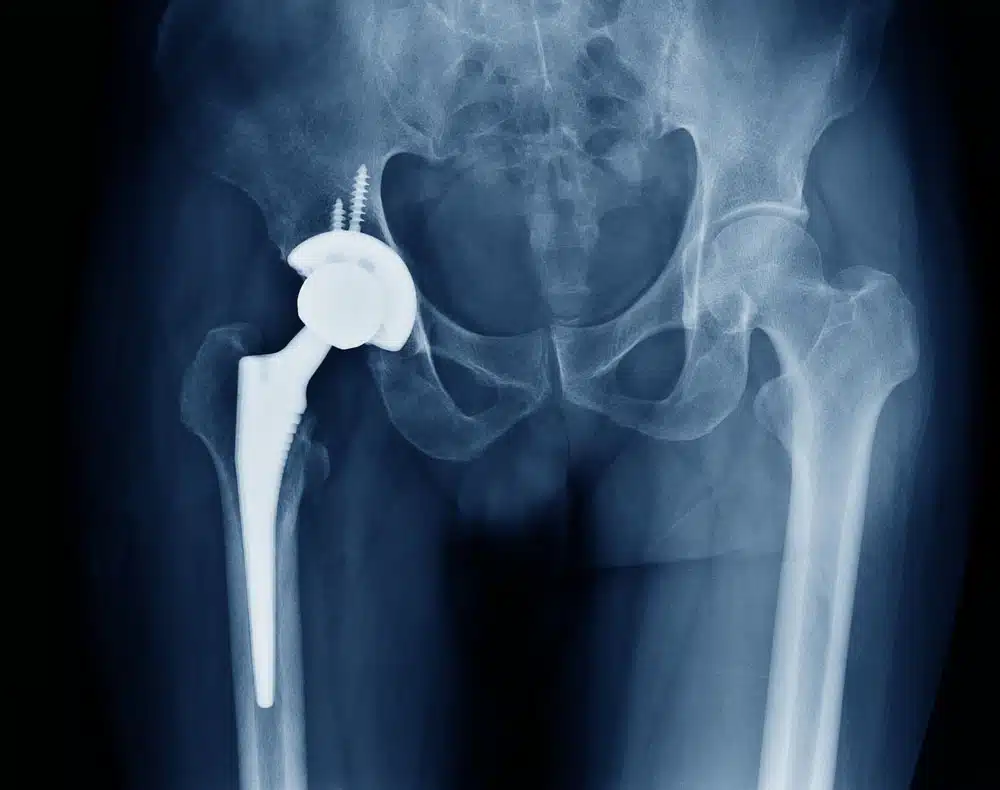

الهدف الأساسي لجراحة استبدال مفصل الورك هو إزالة مفصل الورك المتضرر واستبداله بمفصل اصطناعي. يتم الصاق المفصل الاصطناعي بعظمة الفخذ، الساق والرضفة. يتكون الجزء الملتصق بعظمة الفخذ من معدن صلب وأملس، والذي يستطيع تحمل أوزان ثقيلة ، في حين أن مفصل الرأس مصنوع من السيراميك. علاوة على ذلك ، فإن الأطراف الصناعية في الورك لها فئتان مختلفتان: الأطراف الاصطناعية والدعامات. طرف اصطناعي غير مدعم متصل بالعظم مع سطح خاص بينما سيتم إرفاق الطرف المدعّم باستخدام الملاط الجراحي. في بعض الأحيان يفضل الجراحون الجمع بين هذين النوعين لاستبدال الورك.

كيف يتم إجراء جراحة استبدال مفصل الورك؟

في جراحة استبدال مفصل الورك ، يقوم الجراح باستبدال الطرف العلوي من عظمة الفخذ بكرة مصنوعة من المعدن، وإعادة طلاء تجويف مفصل الفخذ، الذي يقع في الحوض بقشرة معدنية مغلفة بطبقة من البلاستيك. رأس الفخذ هو أعلى جزء من عظمة الفخذ وهو مستدير كروي. عندما يتضرر مفصل الورك من التهاب المفاصل أو الروماتيزم أو لأسباب أخرى ، تحدث الكسور عادة في كل من العظام على شكل وعاء في تجويف الحوض ورأس الفخذ. يقوم الطبيب بتقليم الحافة الغضروفية باستخدام طعوم خاصة، أي إزالة الغضروف المتبقي والعظام الإضافية من التجويف ليشكل نصف كروي كامل.